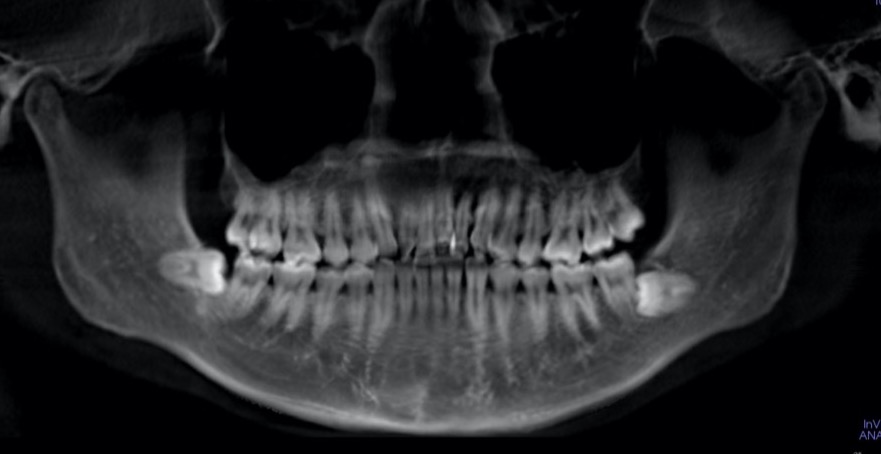

歯根吸収は目で見て分かるものではないので、定期的なレントゲン撮影を行う必要があります。